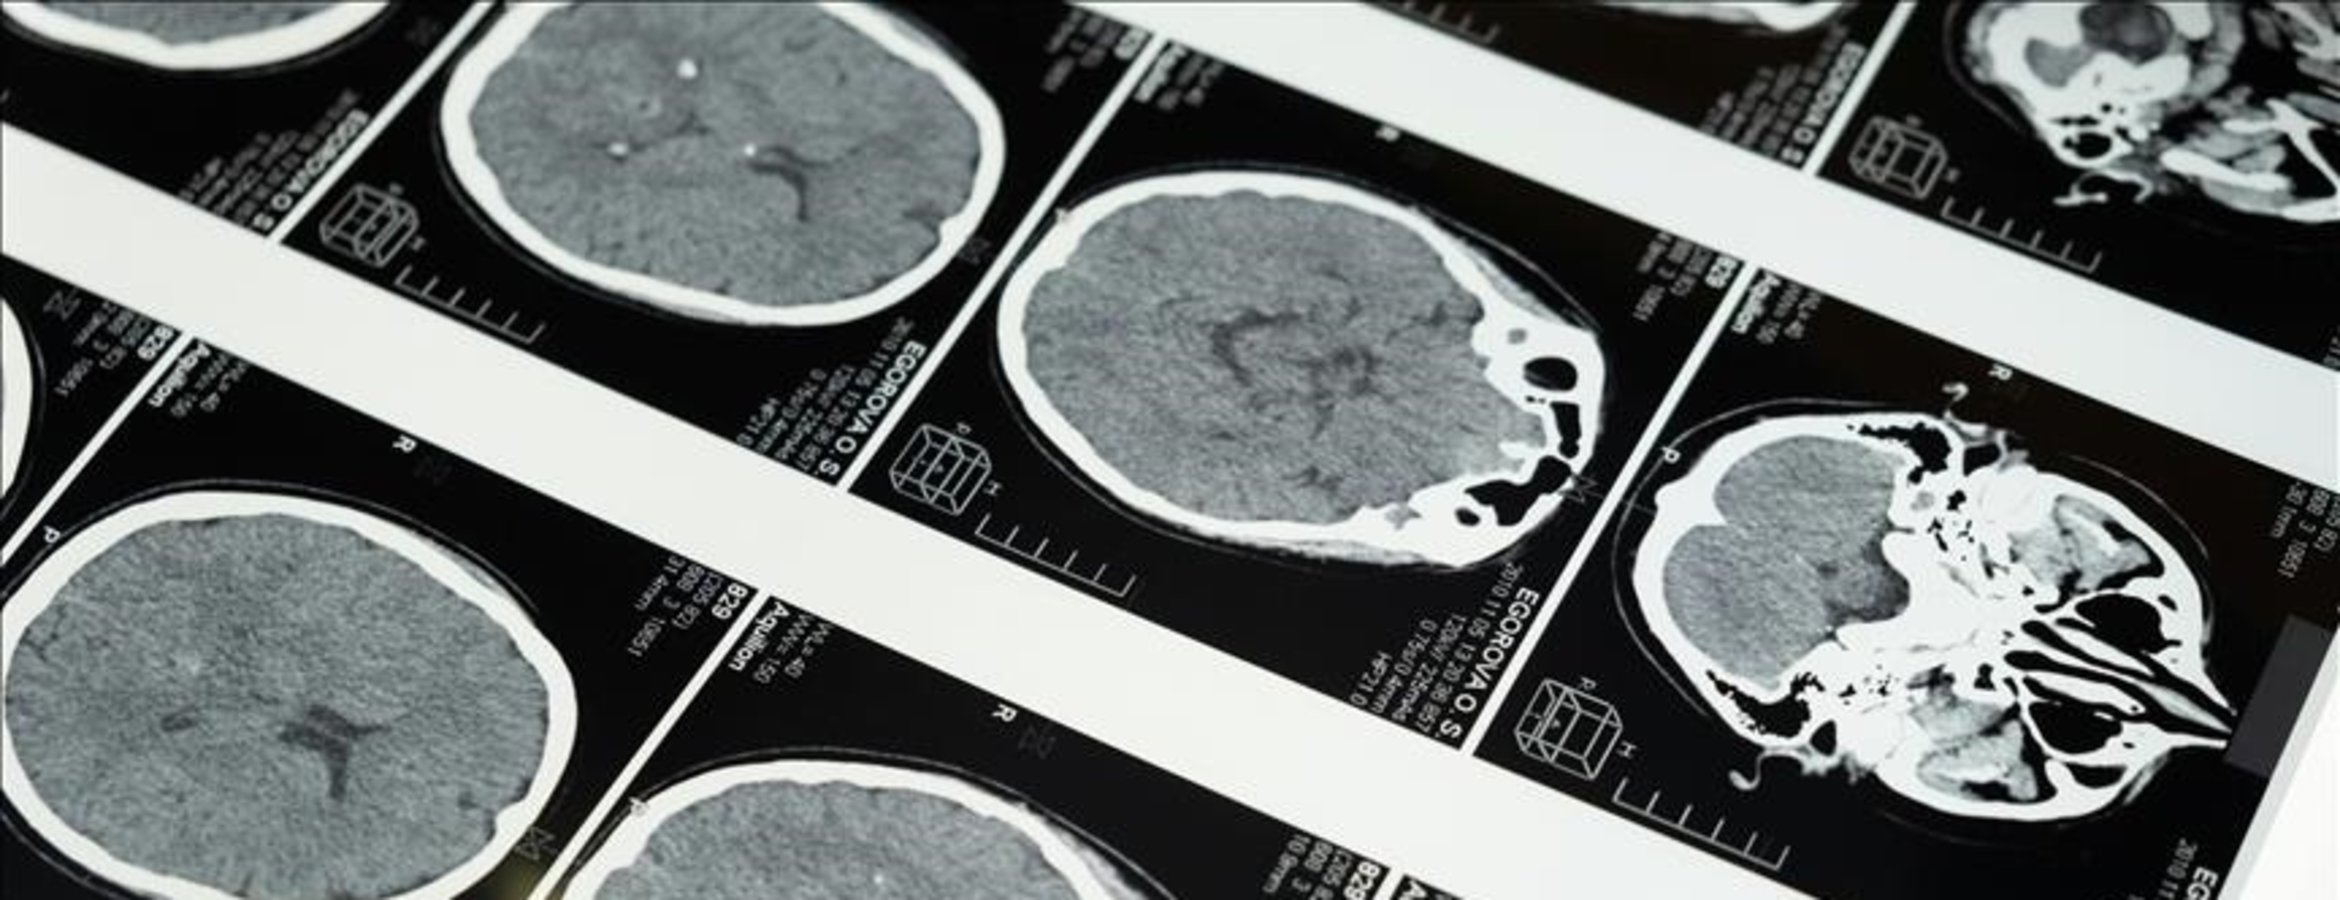

Bilim insanları, geliştirdikleri yeni yapay zeka yazılımı aracılığıyla inme geçiren hastaların beyin taramalarında inmenin ne zaman geçirildiği ve tedavi edilip edilemeyeceğinin normalden 2 kat daha doğru tespit edilebildiğini açıkladı.

Araştırmacılar yazılımın, beyin taramasında ilgili alanı otomatik olarak çıkarmanın yanı sıra, tanımlanan lezyonları analiz ederek inme geçirilen zamanı tahmin edebildiğini tespit etti.